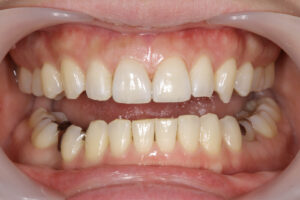

他の歯科医院にてラミネートベニアを施術されたが、ものが詰まる・見た目が良くない・噛めないとのことで治療を希望された。知り合いに当医院を勧められ来院した。

クリーニングの後、上顎前歯2本のラミネートベニア、右下臼歯部にセラミックブリッジを装着した。

治療結果

審美的な仕上がりで、患者自身も満足した。9年経過し良好である。

現在は2〜3ヶ月おきのメインテナンス中である。